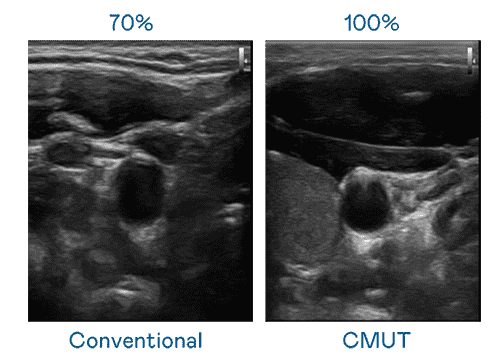

CMUT 技术是一种用电容式微机电元件来产生超音波讯号的技术。。。。与传统 PZT 压电式技术相比,,CMUT 频宽增加 30%,,,更宽频的超音波讯号让影像解析度大幅提升,,,,是实现高影像品质医疗超音波扫描、、促进精准医疗发展的关键技术。。

大频宽带来超清晰影像

超音波影像的解析度高低,,,,首先取决于探头能发出的讯号频宽。。。糖果派对 CMUT 可提供高清晰的超音波讯号,,提供高频宽、、、、高灵敏度、、、影像纹理细节更高的超音波影像,,,,协助医护人员缩短影像判读时间及利用精准的医疗影像进行诊断。。。。